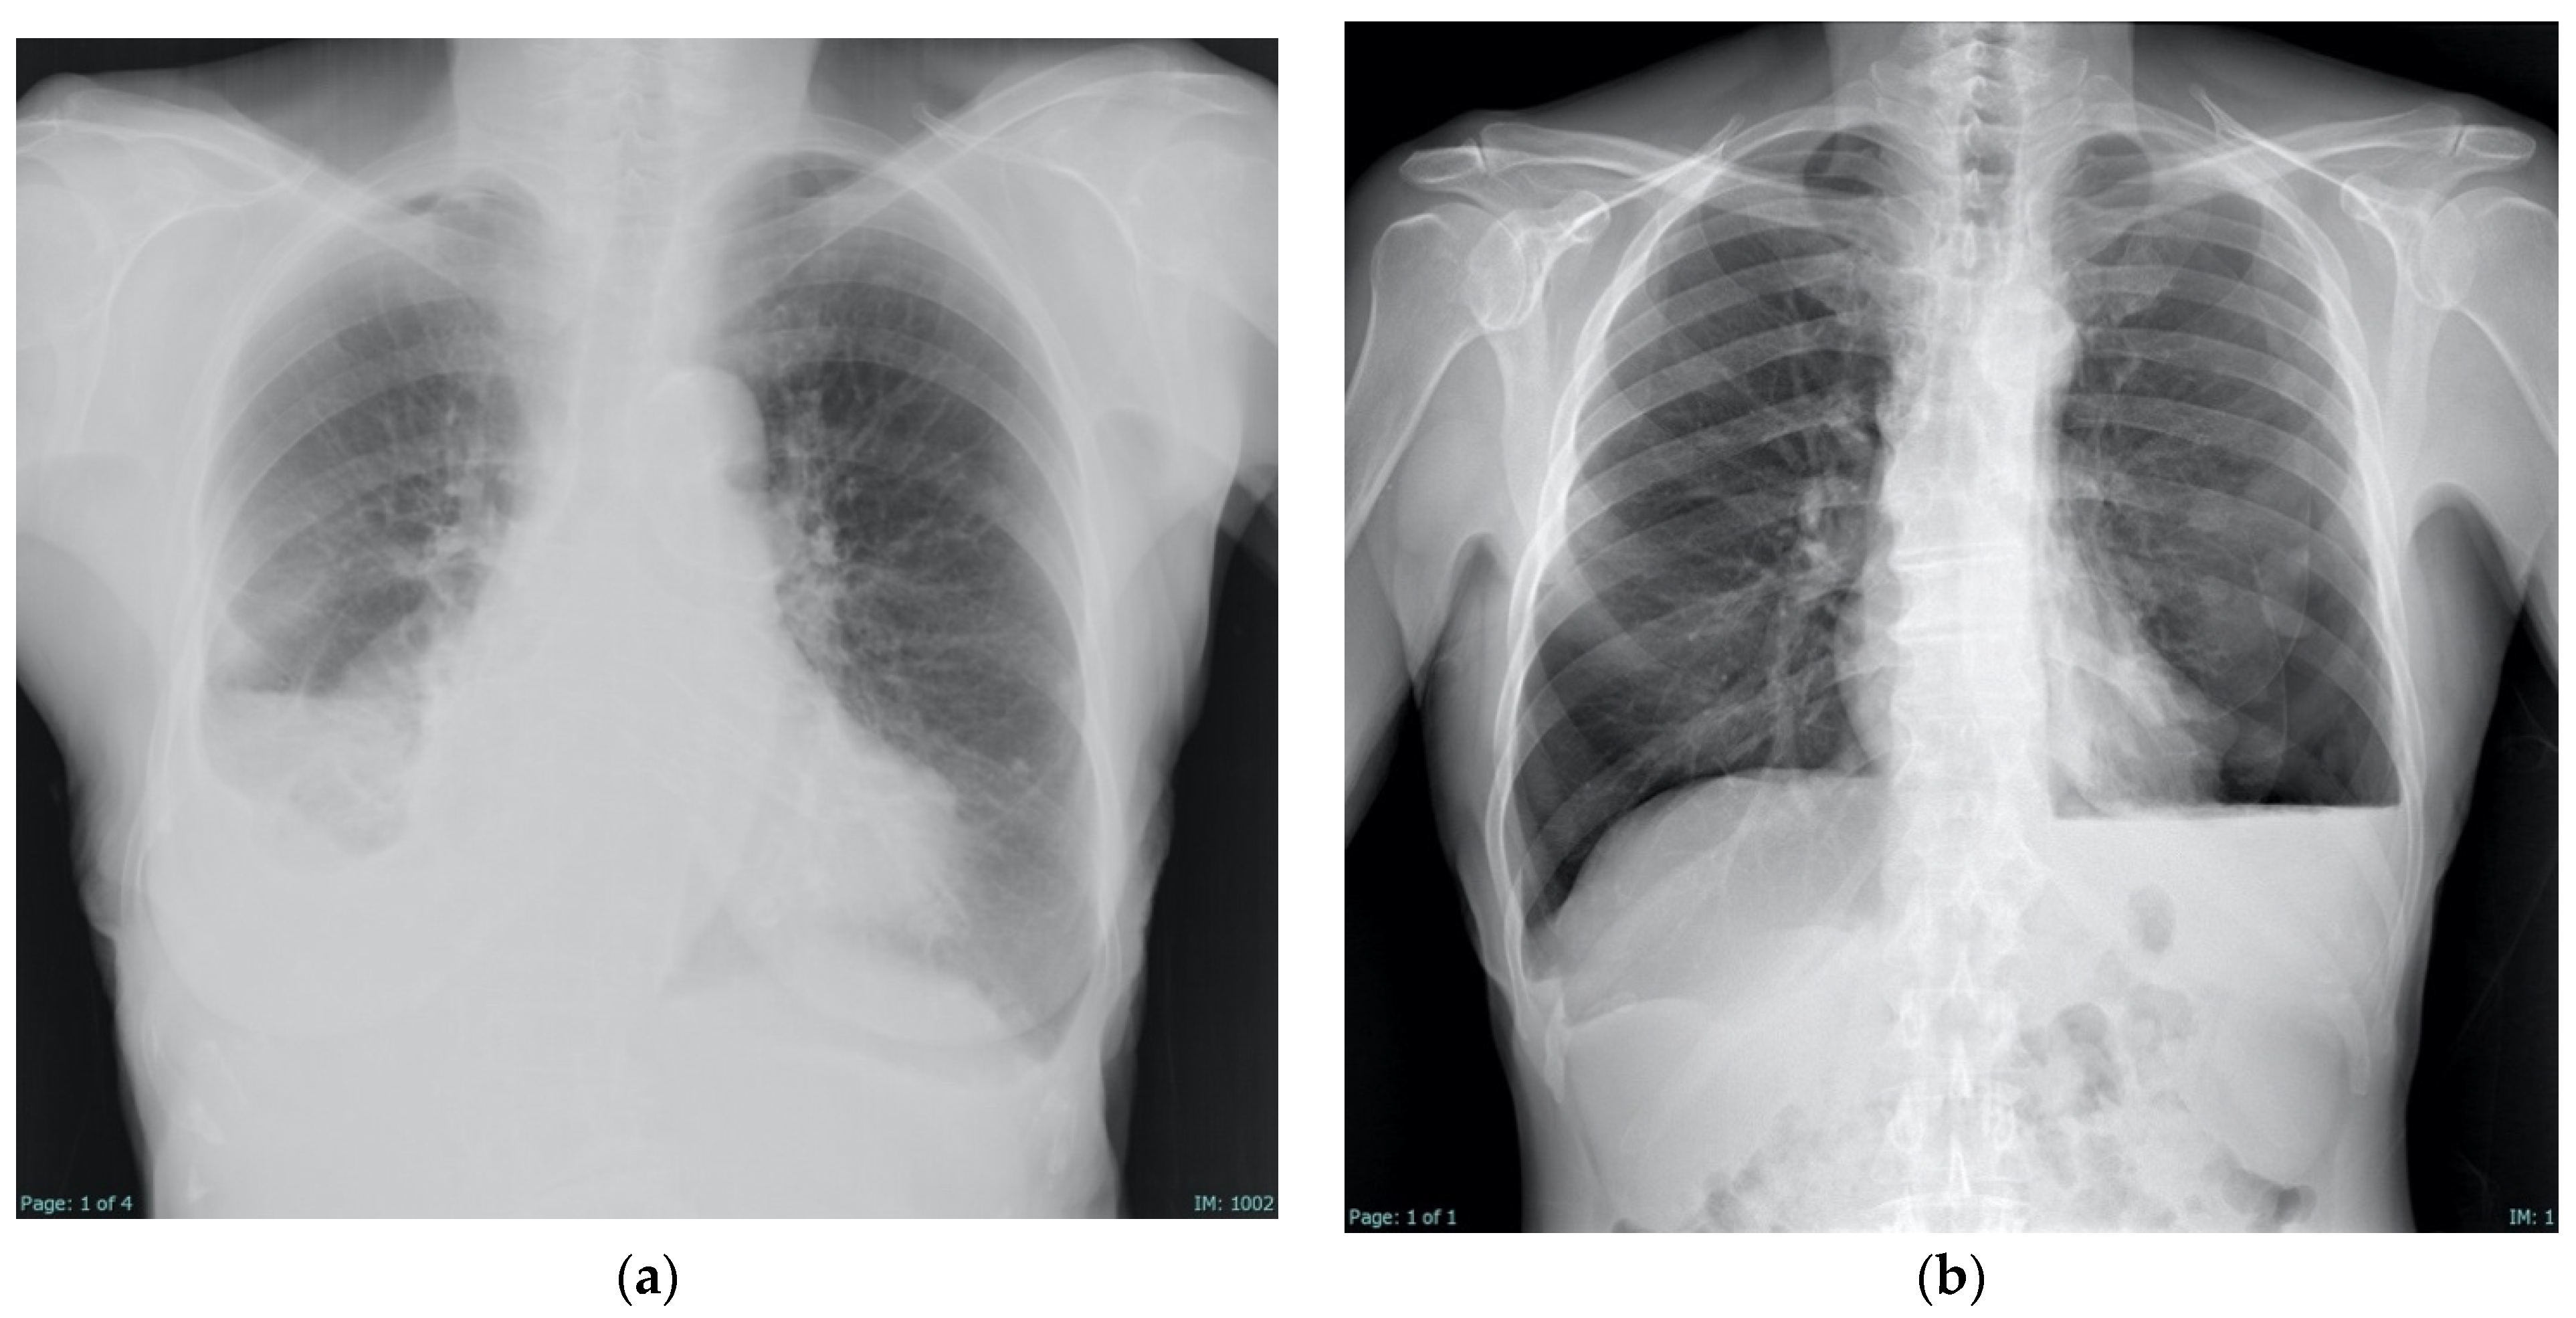

4.3. Radiologic Findings

- Chopra, A.; Judson, M.A.; Doelken, P.; Maldonado, F.; Rahman, N.M.; Huggins, J.T. The Relationship of Pleural Manometry With Postthoracentesis Chest Radiographic Findings in Malignant Pleural Effusion. Chest 2020, 157, 421–426. [Google Scholar] [CrossRef] [PubMed]

- Martin, G.A.; Kidd, A.C.; Tsim, S.; Halford, P.; Bibby, A.; Maskell, N.A.; Blyth, K.G. Inter-Observer Variation in Image Interpretation and the Prognostic Importance of Non-Expansile Lung in Malignant Pleural Effusion. Respirology 2020, 25, 298–304. [Google Scholar] [CrossRef]